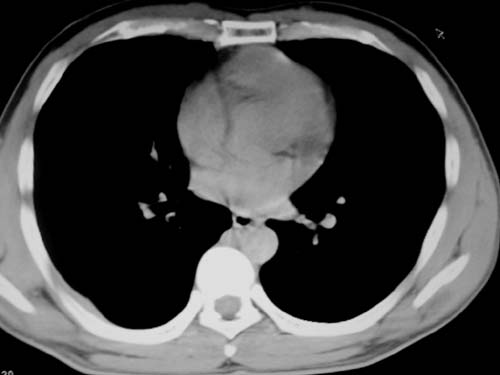

标题: CT19540: 31岁。自述结核性胸水治疗两个月后,在外院拍x线发 [打印本页]

标题: CT19540: 31岁。自述结核性胸水治疗两个月后,在外院拍x线发

右侧胸壁结节状软组织影伴相应肺叶内受侵,伴右侧胸腔积液。考虑:结核性可能大。

1、炎性包块;2、右侧少量胸膜积液。

1、炎性病变,结核可能;2、右侧少量胸膜积液。

右侧胸壁结节状软组织影伴相应肺叶内受侵,伴右侧胸腔积液,结合临床,首先考虑结核。

考虑结核性胸膜炎,胸膜肥厚,不除外胸膜间皮瘤可能,建议复查。

支持结核,胸膜间皮瘤不排除.

1)考虑右侧结核性胸膜结节。2)右侧胸膜增厚+包裹性胸腔积液。

结核性脓胸、肺内结核?